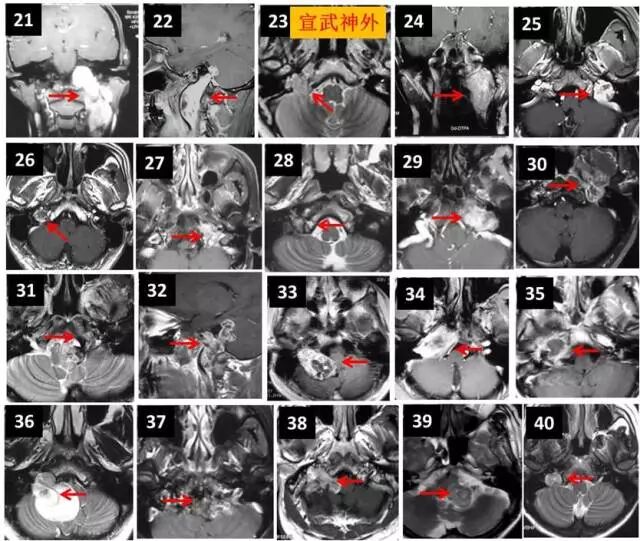

颅底疾病全覆盖

内镜经鼻蝶切除垂体瘤

术前

术后

内镜经鼻蝶切除颅咽管瘤

面神经-舌下神经降支吻合术 修复面瘫

微血管减压术